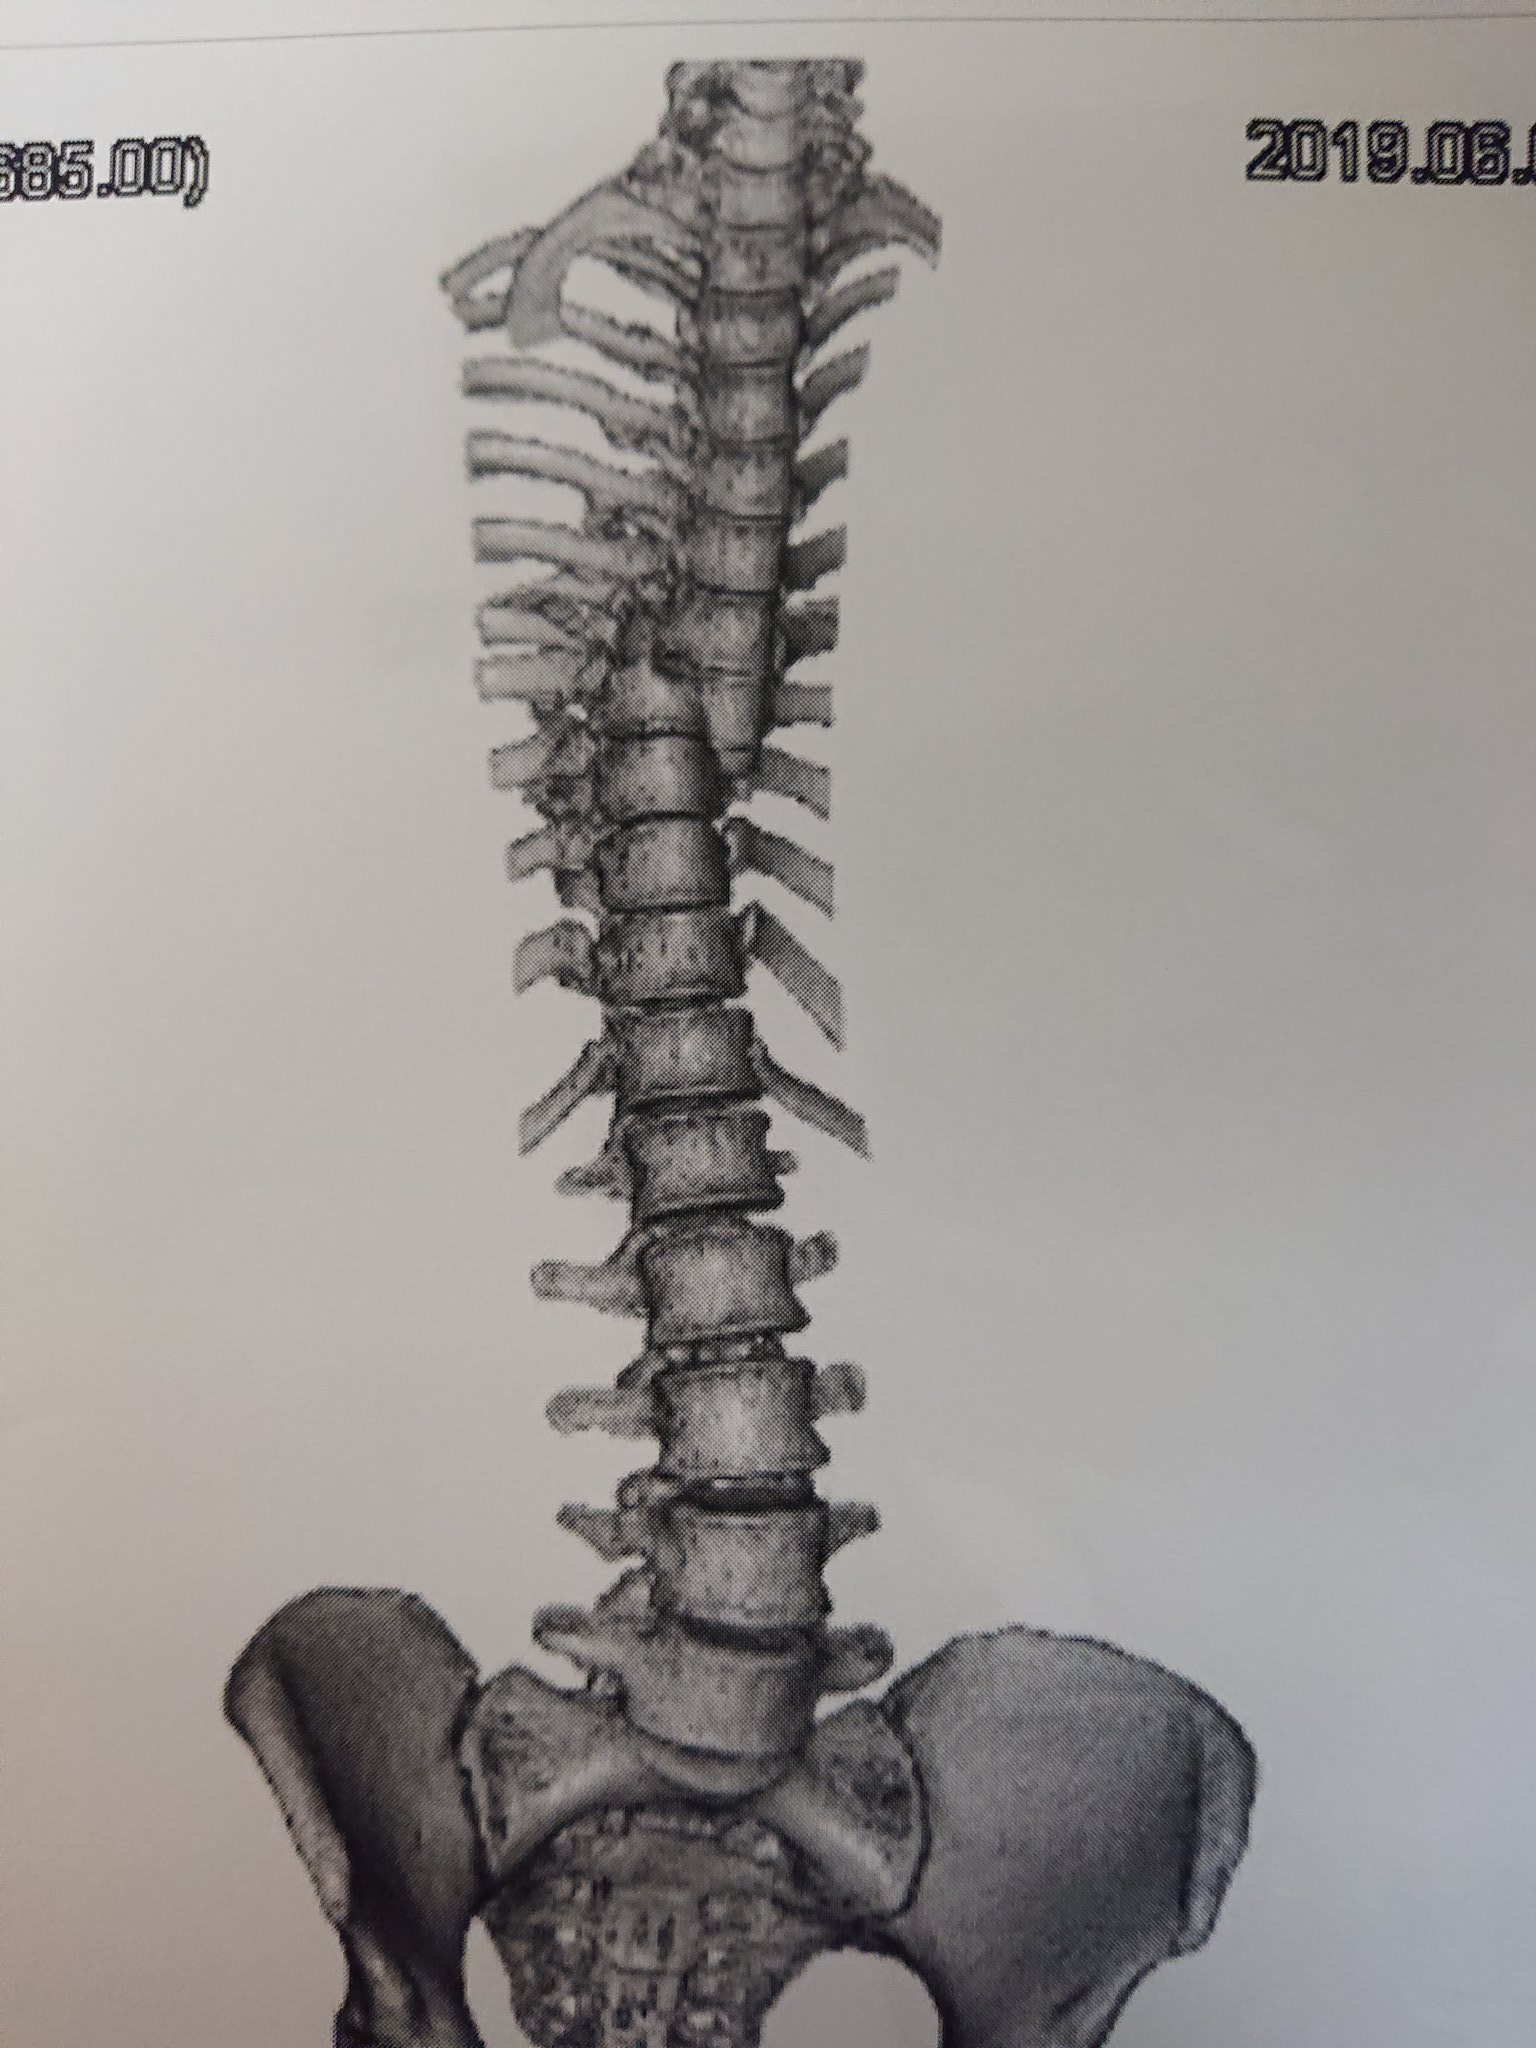

@suma_si

グロ画像注意なんですけど、今日やっと後遺障害申請の診断書を頂くところまで来たので記念アップ。去年の交通事故で運ばれたときの骨。なんでこの状態で下半身不随どころか麻痺すらないのか医者が首かしげてたし、これを神経に損傷与えず手術した先生はマジでブラックジャック。感謝…… pic.twitter.com/jf7oaQPUI4

— ましま (@suma_si) December 3, 2020